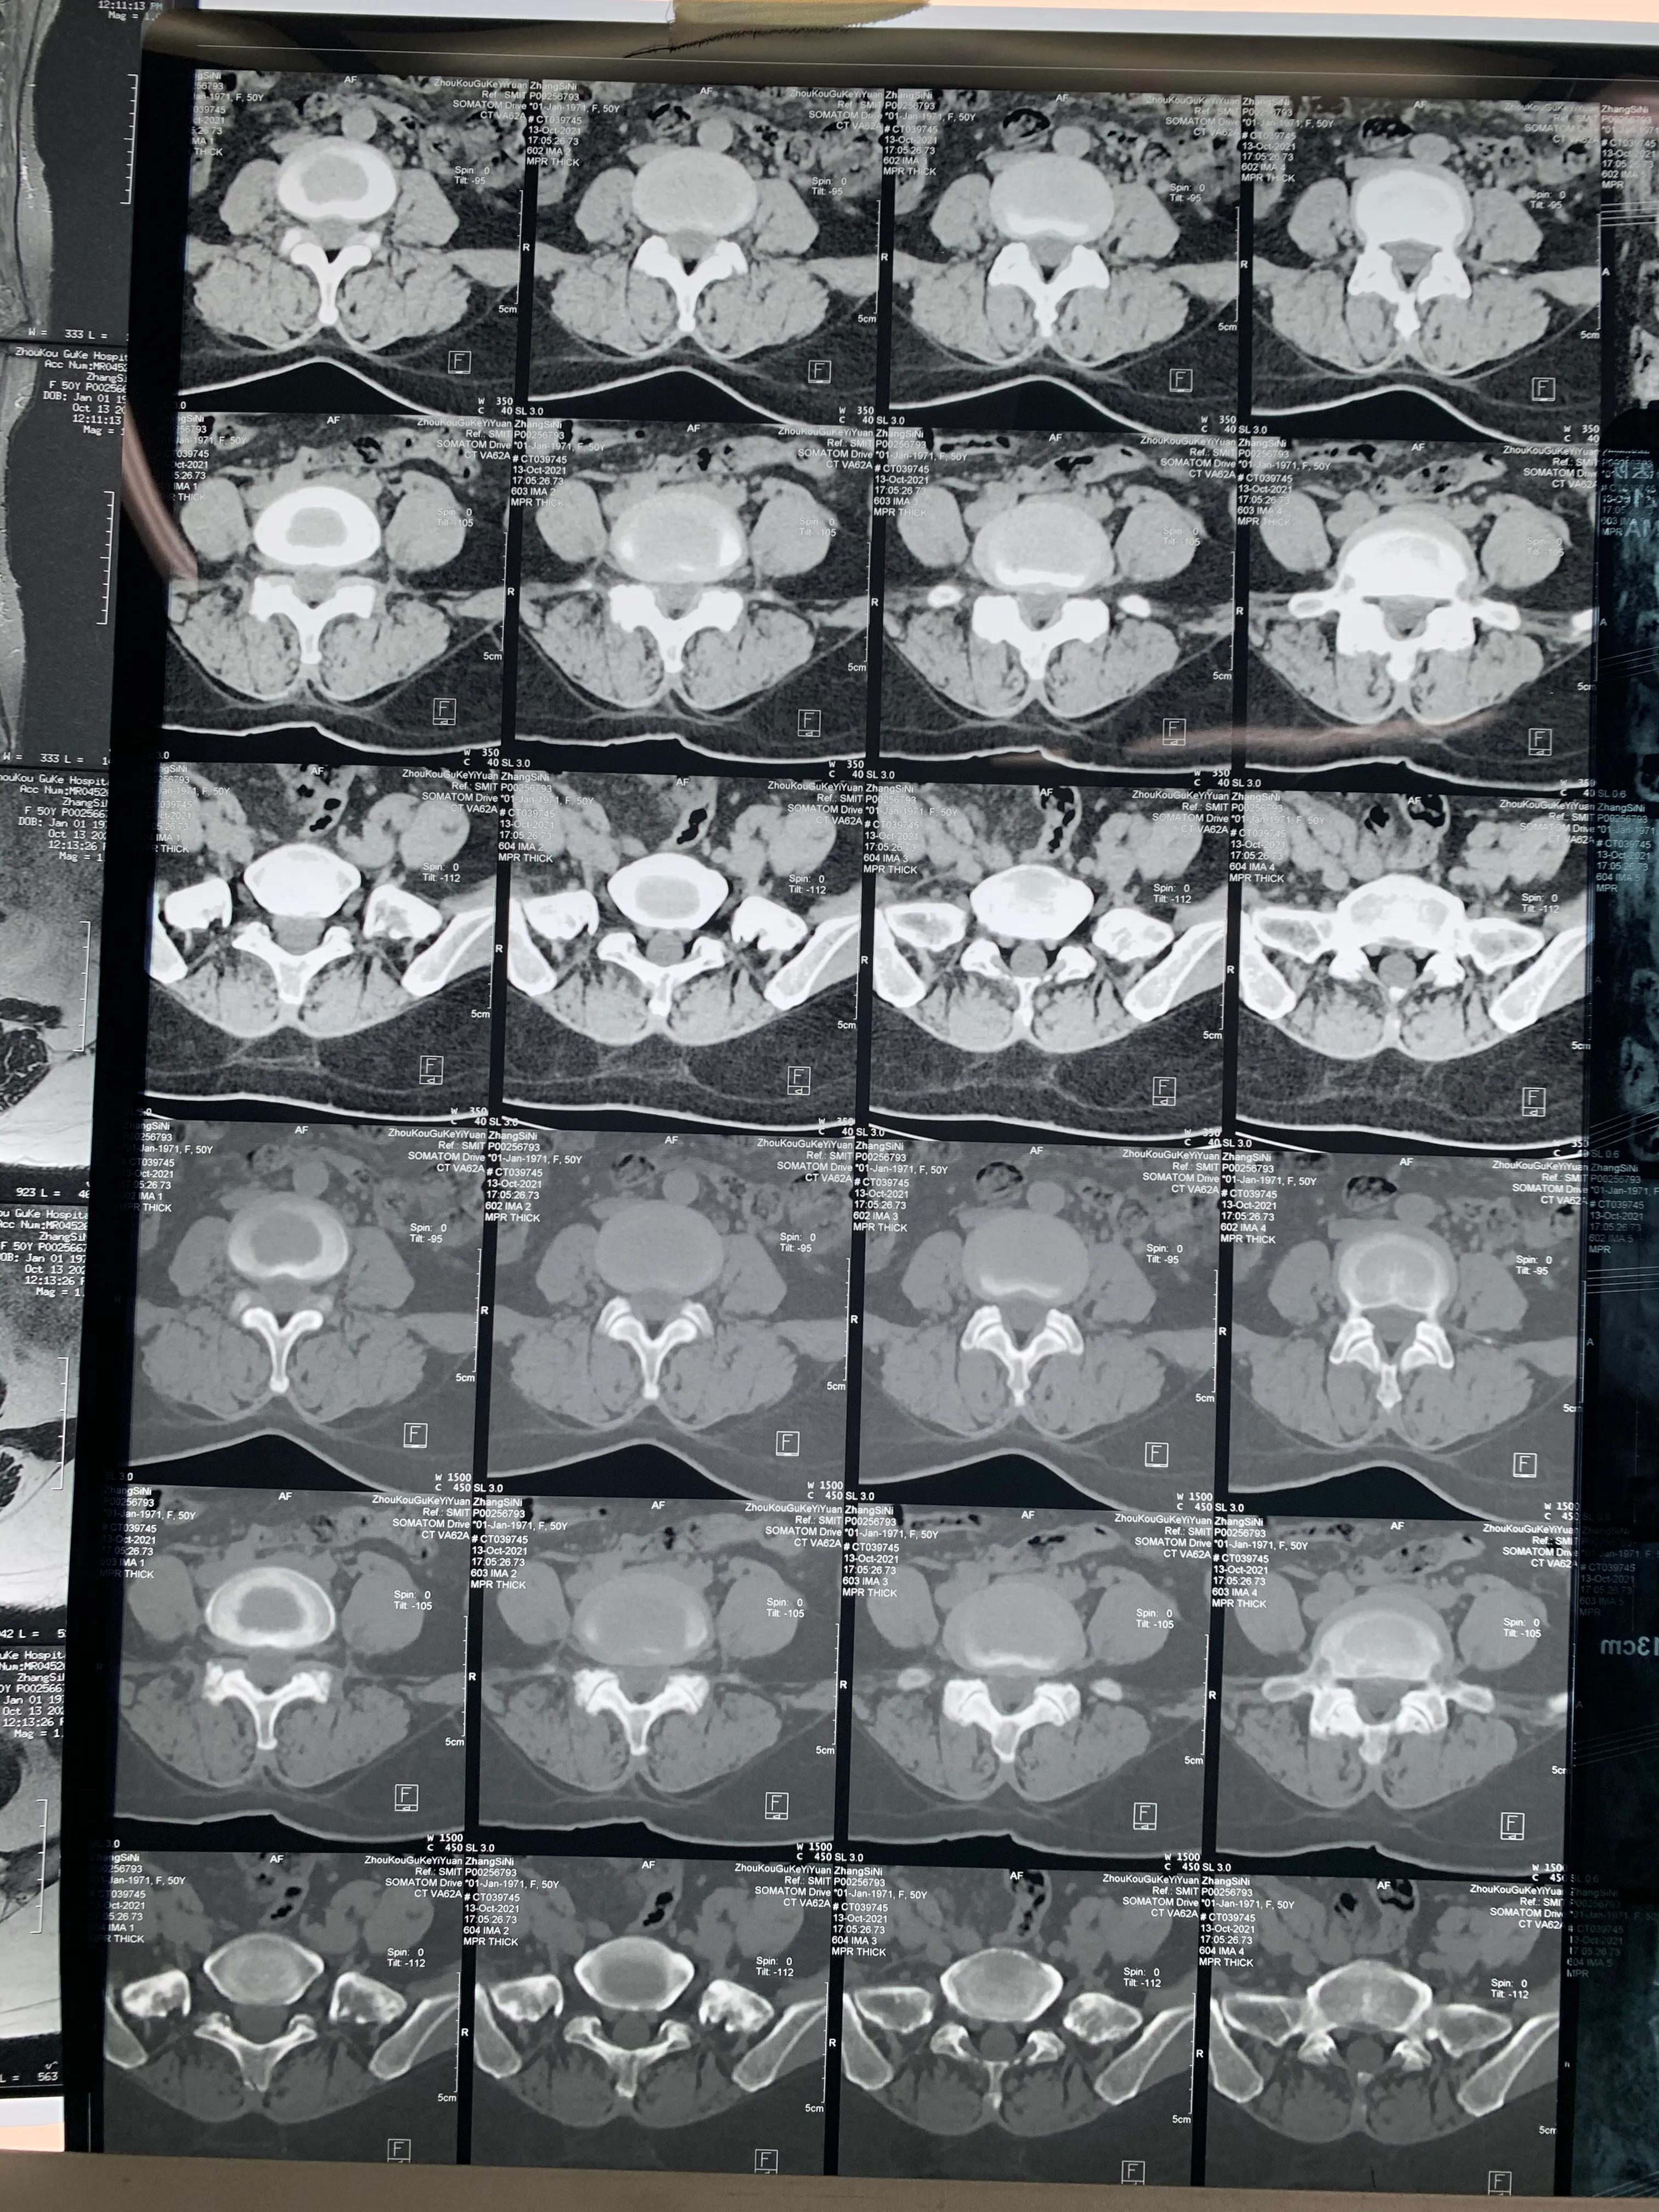

术前体位

进针点

术前定位